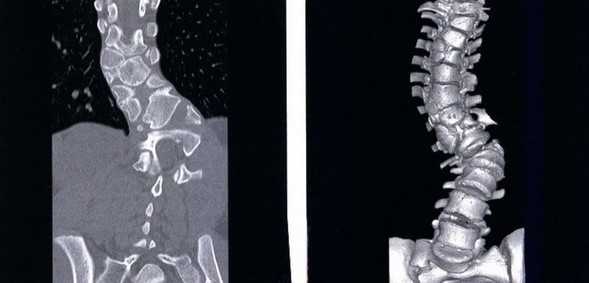

Перелом грудного отдела (трехмерная и сагиттальная проекции)

В результате компьютерной томографии получают серию послойных изображений рассматриваемой зоны. Монохромные фотографии обладают высоким разрешением. В отличие от рентгенографии на снимках отсутствуют дефекты и тени от расположенных рядом структур. Изменение плоскости при реконструкции изображений позволяет тщательно изучить анатомические образования. Преимуществом КТ является возможность создания 3D-модели позвоночника.

Компрессионный перелом (показан стрелкой) поясничного отдела позвоночника

При развитии патологического процесса возникают структурные нарушения, аномалии формы и размеров морфологических элементов.